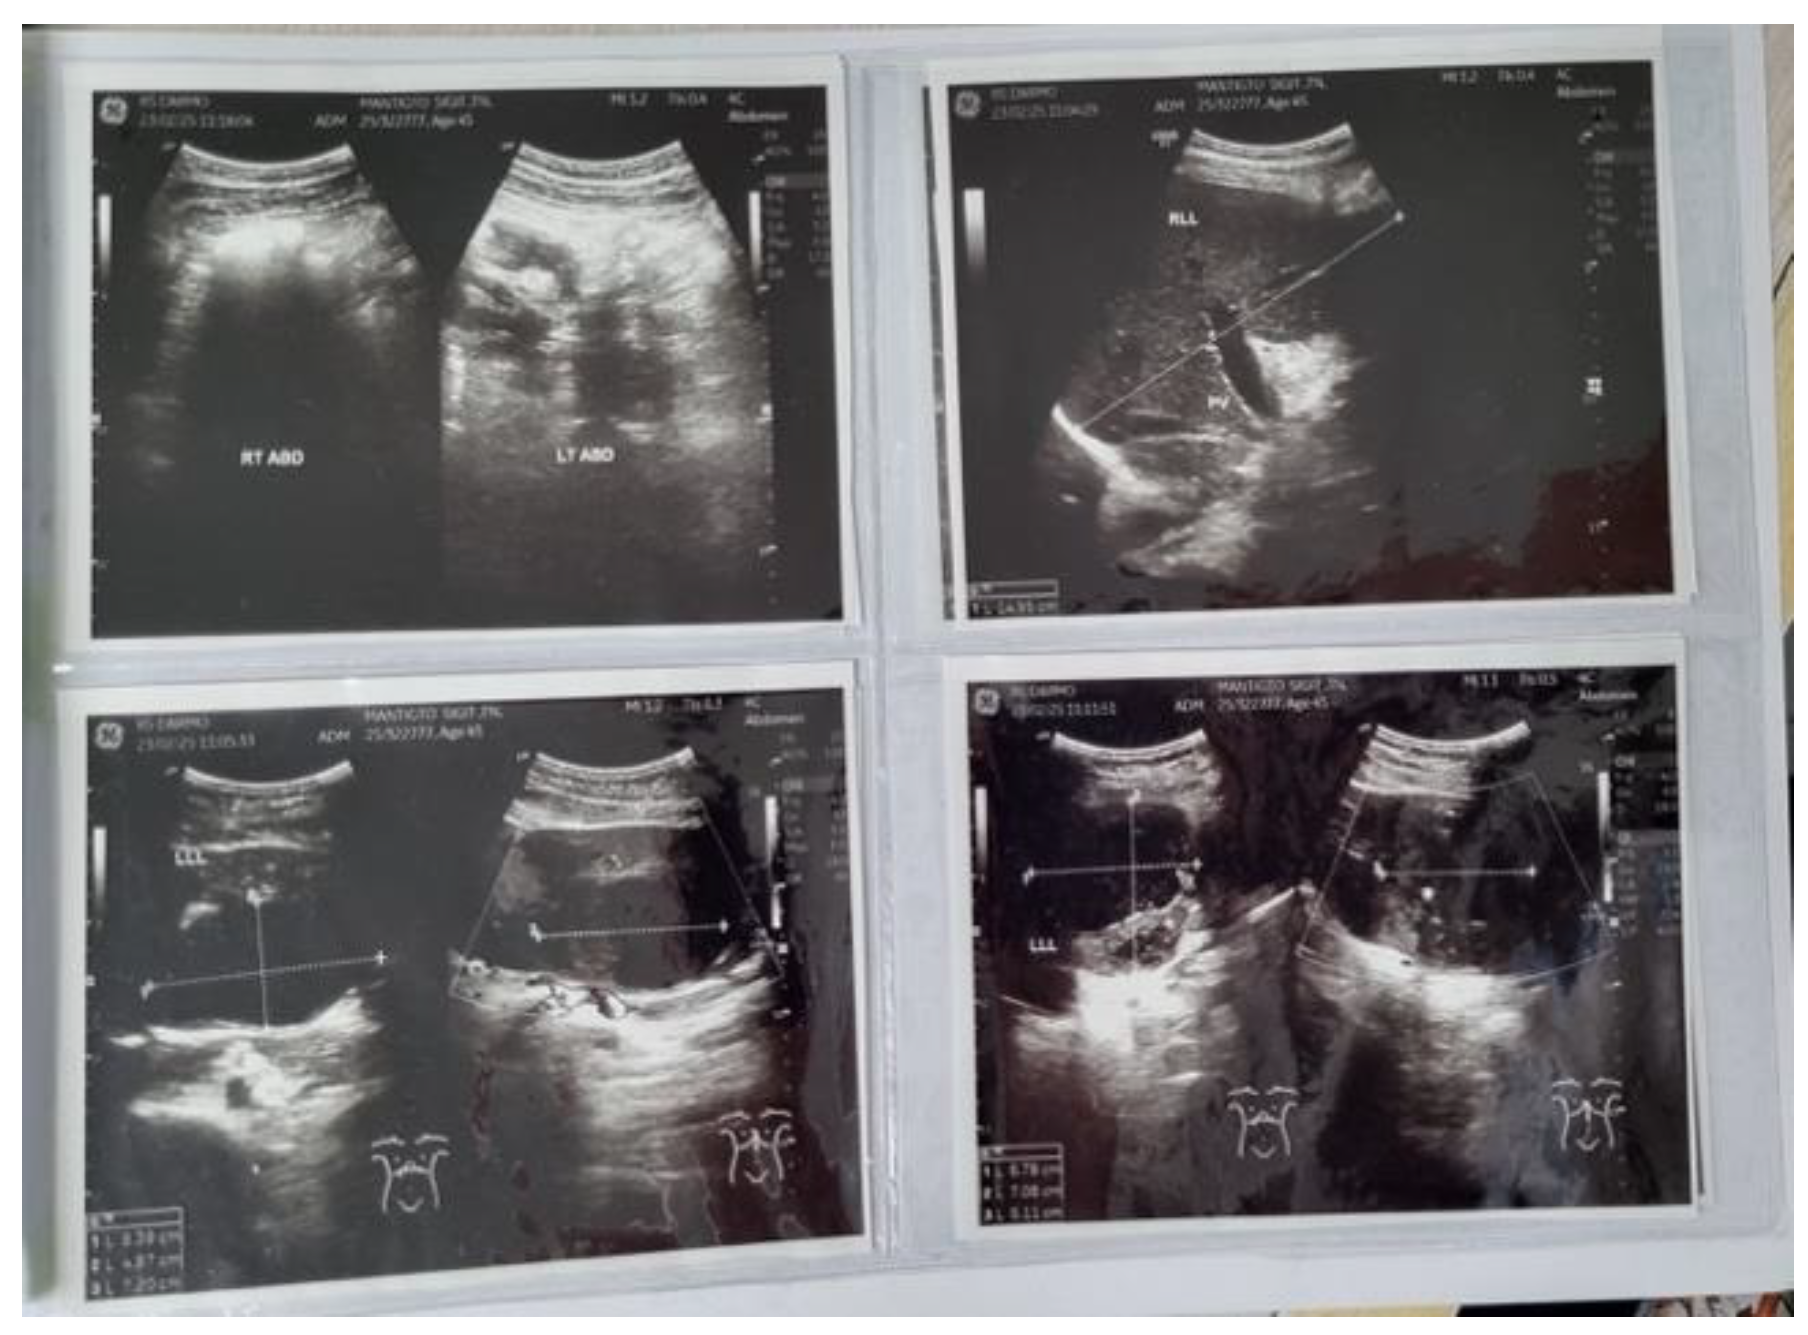

Background: Liver abscesses represent an atypical yet potentially life-threatening complication of bacterial, fungal, protozoal, and helminthic infections. Frequently, the clinical findings associated with liver abscesses are nonspecific, necessitating a reliance on imaging for diagnosis. It is uncommon for a liver abscess to radiographically resemble a malignant liver tumor such as hepatocellular carcinoma (HCC). Here, we present the case of a 45-year-old male who was initially diagnosed with HCC (BCLC C) but was subse-quently found to have a liver abscess following biopsy. Case Presentation: A male patient, 45, presented with stiffness and pain in the right upper abdomen. He complained of nausea and vomiting since 10 days before admission as well. All supportive imaging suggested a diagnosis of HCC. A liver abscess was detected during a biopsy. A liver ultrasound-guided FNAB showcased chronic, suppurative in-flammation with negative acid-fast bacilli on Ziehl-Neelsen staining. The patient sub-sequently developed a complication of middle hepatic artery bleeding and underwent immediate embolization. Discussion: In fact, a liver abscess can be the initial manifestation of HCC. Patients tend to have a poorer prognosis because the diagnosis of a liver abscess often delays the discovery of the underlying HCC. Radiographically, liver abscesses range from well-circumscribed cystic lesions with an enhancing rim to heterogeneously enhancing mass-like lesions, which are sometimes indistinguishable from liver neoplasms. However, it is so scarce that a liver abscess may radiographically mimic HCC. Conclusion: Assessing liver abscess is somewhat complicated since the symptoms vary a lot. Therefore, a correct and exact diagnosis entail a combination of more comprehensive clinical and supporting examinations.